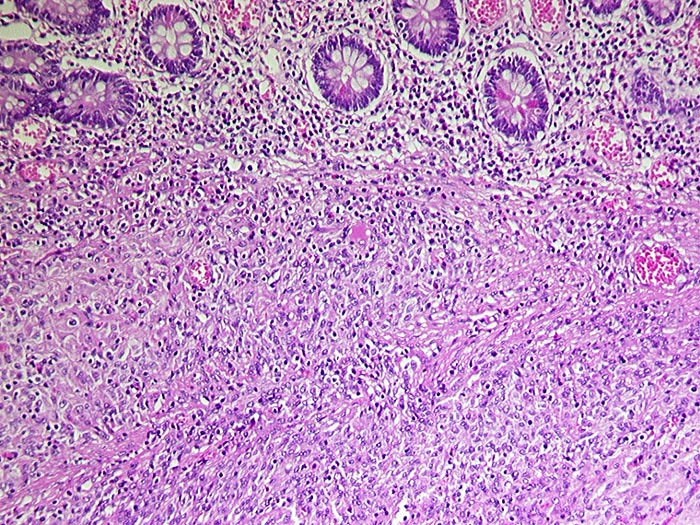

PathoPic ID 1088 - Gastrointestinaler Stromatumor (GIST)

Gastrointestinaler Stromatumor (GIST)

maligner Tumor

Dünndarm

Darm, Anus

Spindelzelliger, von der Submukosa ausgehender Tumor. Die Mukosa wird vom Tumor nicht infiltriert.

Metastasen im mesenterialen Fettgewebe und in der Serosa. S-100 negativ, SM-Actin herdförmig positiv, CD 117 (c-kit) positiv.

Histologie